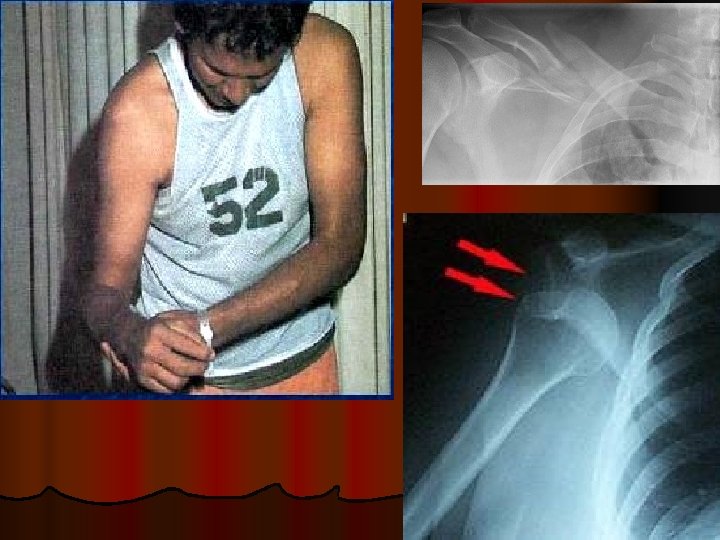

DISLOCATION SHOULDER ANTERIOR RECURRENCE

l Axillary nerve injury Deltoid wasting

FRACTURE CLAVICLE